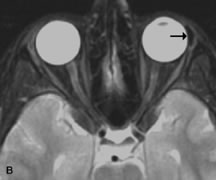

Fig. 18. A. T1-weighted, (B) T2-weighted fat-suppressed, and (C) T1-weighted fat-suppressed MR scans demonstrate a small dermoid cyst arising near the palpebral portion of the lacrinal gland (arrows). The lesion is similar in signal intensity to fat on the T1-weighted scan (A) consistent with a high adipose tissue content. The lesion shows fat-suppression and low signal intensity on the two fat-suppressed sequences (B and C) confirming its high lipid content.

Dermoid cysts appear as rounded, well-defined lesions typically contiguous with an orbital bony suture. The high-intensity signal on T1-weighted images is attributed to the sebaceous-produced lipid contents (Fig. 18).31,50 Mucoceles may demonstrate a hypointense or hyperintense signal on MR images, depending on the concentration of proteinaceous or inflammatory fluid components. The integrity of the bony walls of the expanded sinus cavities cannot be assessed on MR as well as by CT.37,50,55,56 A high-signal intensity on Tl- and T2-weighted images is characteristic of orbital chronic hematic cysts because of the blood-breakdown products within the cysts.57